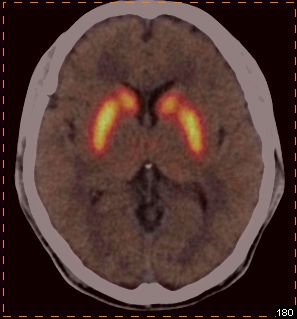

我科使用11C-CFT进行脑部多巴胺受体显像

PET/CT示:

双侧尾状核、双侧壳核放射性摄取对称,未见明显减低

根据PET图像,最终排除帕金森病